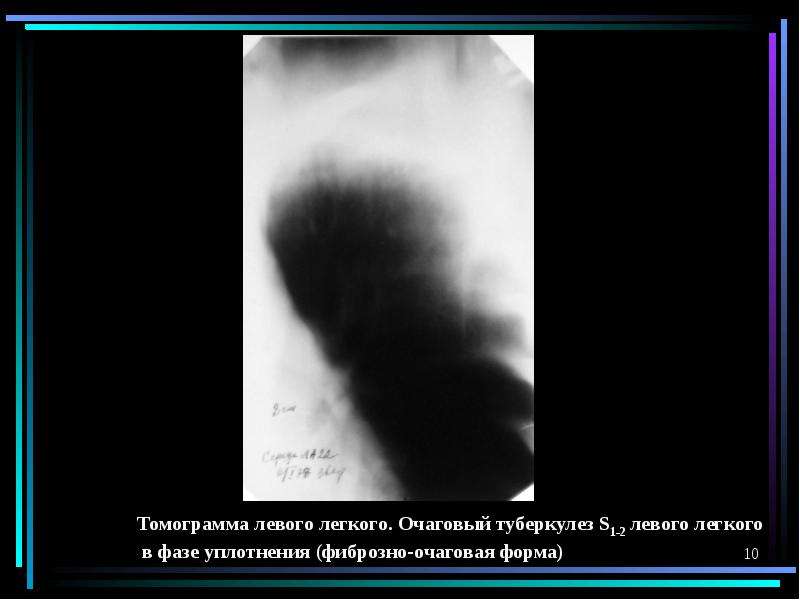

Очаговый и инфильтративный туберкулез презентация - 94 фото